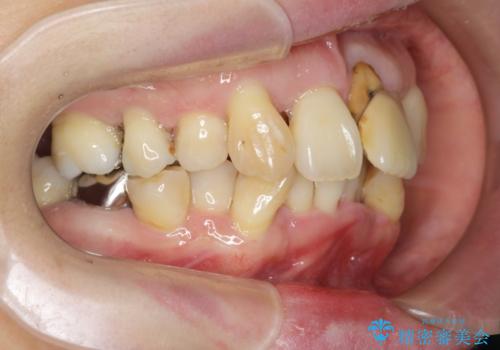

- 重度の歯周病に罹患しており、他院で「多数の歯を抜歯したのち、入れ歯を入れるしかない。」と言われ、入れ歯以外の方法がないか相談のため来院されました。

重度の歯周病で多数の歯を残せない問題、歯並び・噛み合わせの問題、欠損の問題、と多数の大きな問題が認められました。

このままの歯並びでは仮にインプラントを埋入したとしても歯ブラシがしづらく、また歯周病の問題が再発しやすい、と判断し矯正治療を行ったのちに歯周病治療、インプラント治療を行っていく治療計画としました。